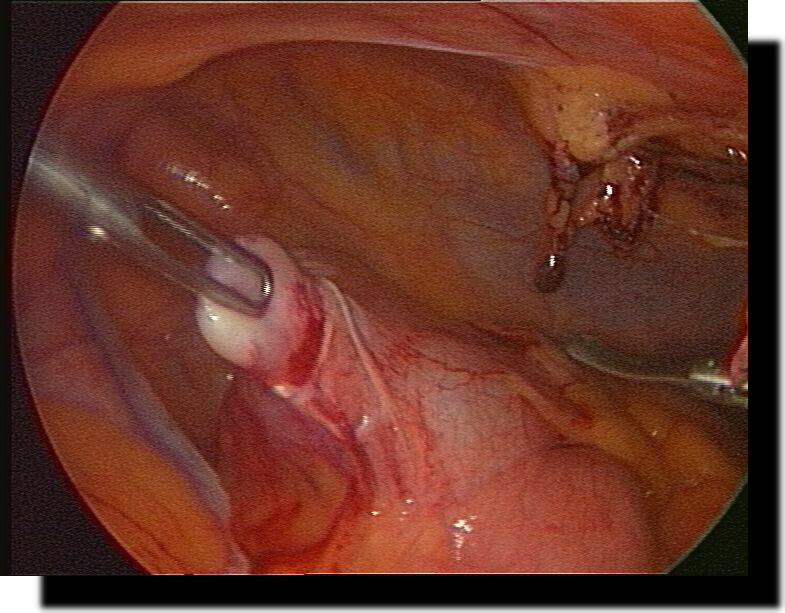

Magenperforation

Z.n. laparoskopischer Ulcusbiopsie und Magenperforations-Übernähung